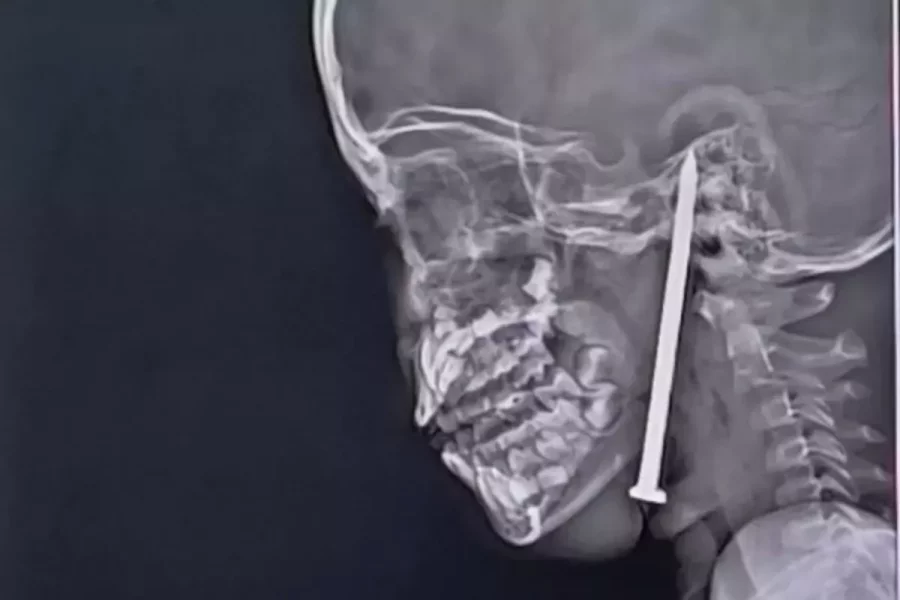

Uttar Pradeş ştatında oyun oynayarkən yıxılan 7 yaşlı qızın boynundan daxil olub çənəsini və beynini deşən 8 santimetrlik mismar həkimlər tərəfindən uğurla çıxarılıb.

Tomoqrafiya nəticələri mismarın həyati damarların çox yaxınlığından keçdiyini göstərib. Əməliyyat 16 mayda Lakhnaudakı Kral Corc Tibb Universitetində neyrocərrahlar Vaibhav Jaiswal və Sameer Mishra tərəfindən həyata keçirilib.